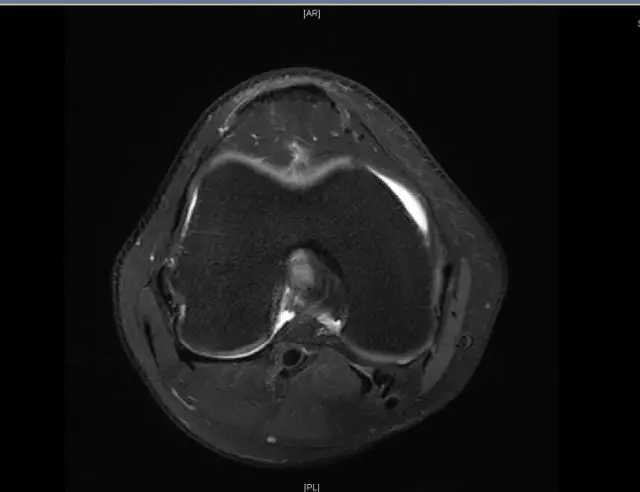

前交叉韧带断裂,外侧半月板后角撕裂

从此片我们可以看到前交叉韧带的上止点高信号,前交叉韧带角度增加,后交叉韧带的夹角增大,从这个层面可以看到外侧半月板边缘不清楚不完整质地不均一,混杂有高信号的改变,并且内部有一些裂隙,从这个层面我们可以看到前交叉韧带的下止点相对比较完整,而这个层面上止点信号异常,韧带松弛并且有大量的渗出病变,缺乏张力。这个层面也可以看到髁间窝这个部位凸起,看不到应有的上止点信号。所以这个病例我们需要考虑前交叉韧带断裂,外侧半月板后角撕裂。